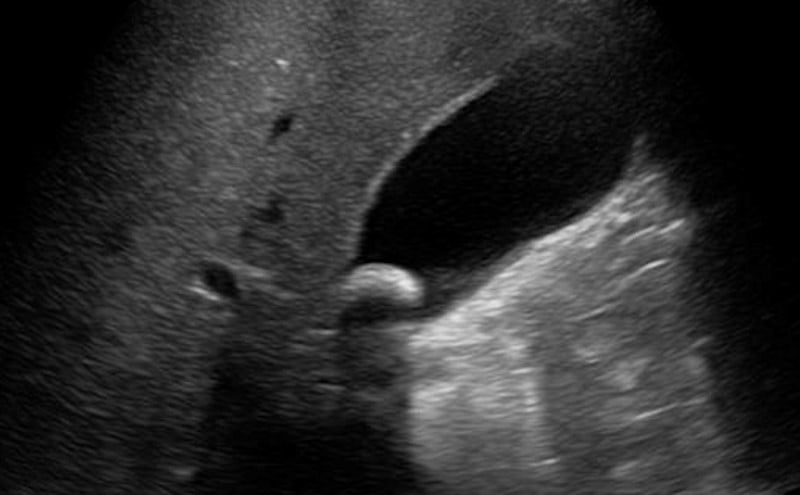

• Figure 1-GB single stone neck.jpg

• Figure 1: Solitary stone in gallbladder neck